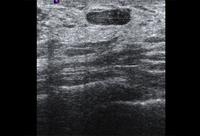

Imagen en ultrasonografía de un carcinoma invasivo

Cortesía del Dr. Lane Roland, University of Louisville; utilizada con autorización

Ver esta imagen en el contexto de la/s siguiente/s sección/es: